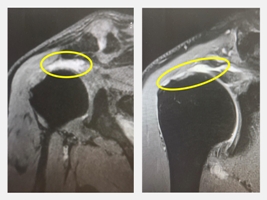

65歲的阿嬌姨是大甲媽信徒,自小就在台中外埔種稻和芋頭,一點一滴拉拔七個小孩養大成人,因歲月不饒人,逐漸出現膝蓋痛和腰痛的毛病,所以決定不再種田,四處遊山玩水,偶爾自己下廚。某次煮飯完正在洗鍋子時,忽然肩膀一陣痠痛,然後就無法舉起,驚嚇之餘趕緊到藥房買藥,又找中醫推拿整復,肩膀卻越來越痛,依舊徹夜難眠,全家也夜夜不得安寧,後來由家屬陪同到仁愛長庚合作聯盟醫院(大里仁愛醫院)骨科葉文凌教授門診求診,經核磁共振檢查後發現竟是右肩旋轉肌破裂。阿嬌姨接受關節鏡雙排縫合手術後,隔天即出院,第二天下午去大甲媽還願,第三天還開車到北港,預計復健仍要三至六個月,生活功能幾乎沒受到影響。

葉文凌教授指出,所謂旋轉肌是肩膀上端四條肌肉的總稱,主要是脊上肌、脊下肌、肩胛下肌和小圓肌,在肱骨頭會融合成一條「共同肌腱」。組織上,尤其重要的是前二者,主要功能是和三角肌共同負責抬起肩膀和左右擺動。「共同肌腱」必須承受巨大壓力,所以很容易老化,60歲以上約有3 0%會有無症狀的破裂,此時未必有手術必要,主因是三角肌代償功能良好。一旦發生某些原因,如扭傷、外力影響,可能會開始有症狀,這代表代償機制已經不行了,所以發炎序列加重,疼痛會漸漸加劇,隨之而來的是肌腱破壞加速,肩關節功能也漸漸下降,終至不得不治療。值得注意的是,約有四分之一的病人是兩側同時破裂,但未必有症狀。

葉文凌教授表示,如果只是小於1公分的破裂,仍可以保守治療,不論增生治療、PRP、羊膜、幹細胞及衍生物、外泌體等,均有一定效果。若破裂1至3公分需要縫合,須使用錨釘作單排或雙排縫合,3公分以上則須看肌腱品質,可以縫合、重建旋轉肌、或使用反式人工關節。目前縫合的趨勢是微創手術,在關節鏡手術下使用雙排錨釘縫合,如此穩定度較好,病人可以提早活動。但是由於旋轉肌破裂的本質就是一種組織老化,所以縫合問題除了手術技術外,術後縫合組織會不會癒合也是十分嚴峻的考驗。目前的趨勢是必須使用生物技術加速癒合,如生長因子、細胞外基質、幹細胞及衍生物等。